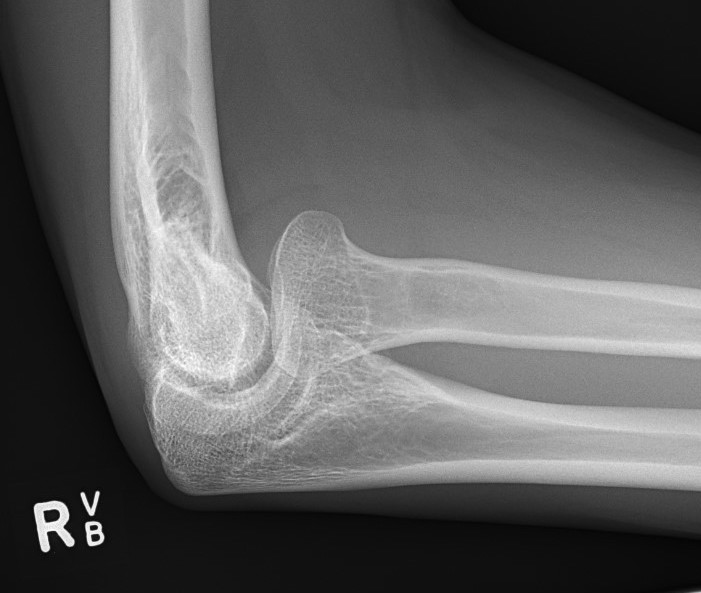

Case 2. Chronic Monteggia with deformed radial head

- radial head can become malformed over longer periods of dislocation

- recommend no surgery if radial HEAD is deformed on CT